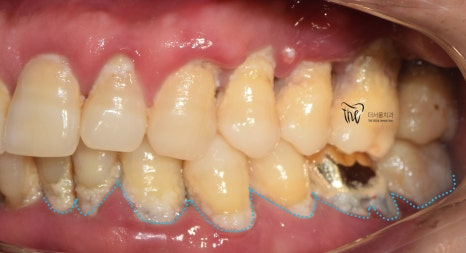

일전부터, 치아 사이 충치 관련 글을 수 없이 많이 적어왔었죠. 영어로는, Proximal caries 라 부르며 조금 더 전문 용어로

구강 내에 어떠한 작은 문제가 있으면, 이를 그대로 두지 말고 빠르게 처치하는 게 좋습니다. 원래 조그만 것이 서서히 눈덩이처럼